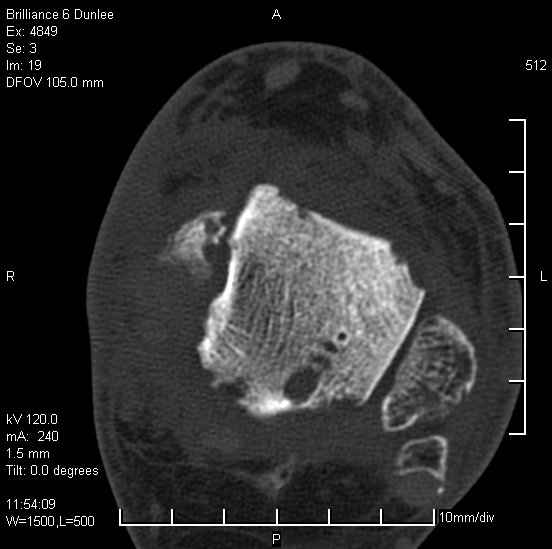

Асептический некроз таранной кости.

На лечении находится пациент 35 лет. Травма в сентябре 2008 г.- открытый вывих таранной кости

В день травмы ПХО, вправление вывиха, трансартикулярная фиксация. Рана зажила первично. С января нагрузка на конечность. С конца апреля- болевой синдром. На рентгенограммах и КТ признаки ас. некроза таранной кости, артроз подтаранного и голеностопного суставов.

У больного тотальный ас. некрох блока таранной кости, заинтересованы голеностопный и подтараный суставы. Эндопротезирование маловероятно на некротизированную кость. Изолированный подтаранный артродез таран не спасет.При артродезе всю некротизированную кость придется убрать.А далее замещение либо за счет большеберцовой кости, или удлинение на регенерате.